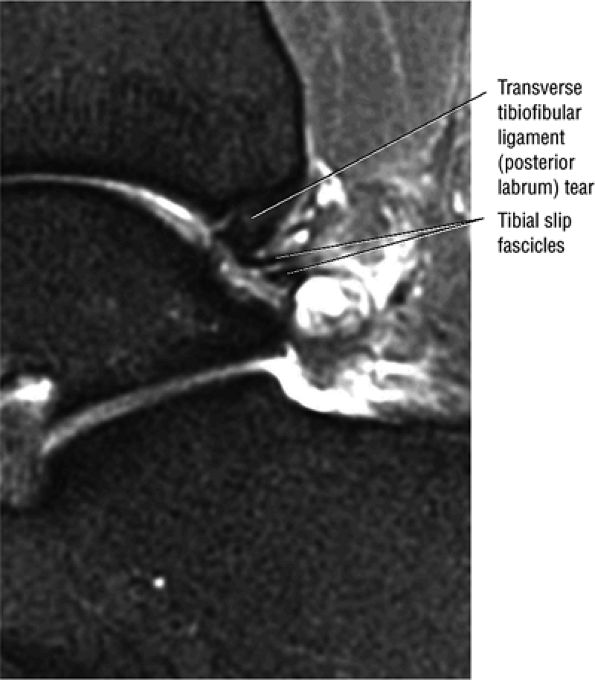

The syndesmotic ligaments consist of the anterior syndesmotic or anterior inferior tibiofibular ligament and the posterior syndesmotic or posterior inferior tibiofibular ligament, the interosseous membrane, and the transverse tibiofibular ligament.

-

The transverse tibiofibular ligament represents the posterior labrum of the ankle and projects inferior to the posterior tibial margin.

The tibial slip is the posterior intermalleolar ligament.